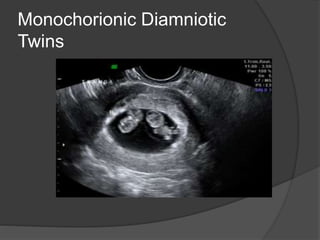

Monochorionic Diamniotic

Twins

Multiple Pregnancy  Multiplepregnancies and types of twinning depends on the number of zygotes and timing of division and they are : 1- Dizygotic twins : two fertilized ova and they are all dichorionic , diamniotic 2- Monozygotic twins : the amnionicity and chorionicity depends by the time of zygote division - Before 3rd day post conception : diamniotic, dichorionic - 4th-8th day post conception : monochorionic , diamniotic - Cleavage of the inner cell mass of blastocyst after 8th day post conception : monochorionic, monoamniotic. - Incomplete cleavage of embryonic disc after 13th day post conception : conjoined twins